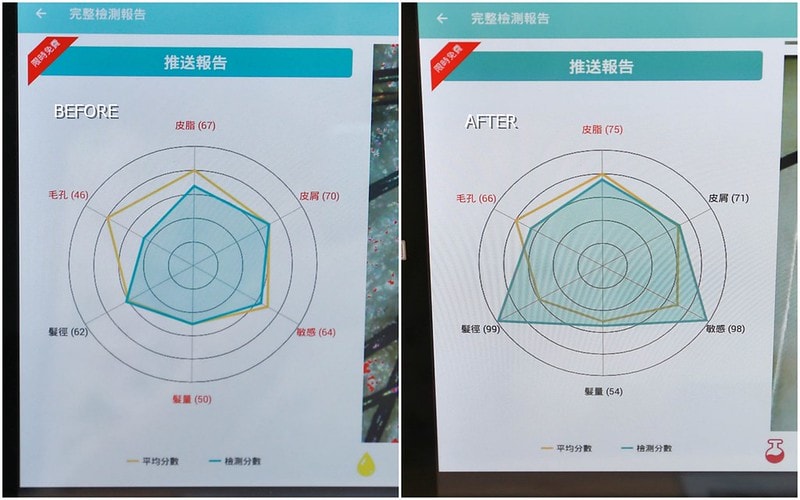

數據變化才是最明顯的了

原本幾乎是一片紅字哈哈哈

很像上學時後被打不及格那樣

課程完之後覺得很有感

但是要比較完整的改善

至少要五到六次課程以上會更明顯喔!!!!

我覺得對我來說改善最多的應該是敏感部分

原本頭皮很紅的,課程完真的舒緩很多